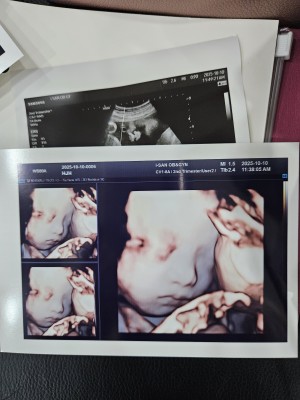

28주 히또초음파예요!

푸히또

2025-10-15